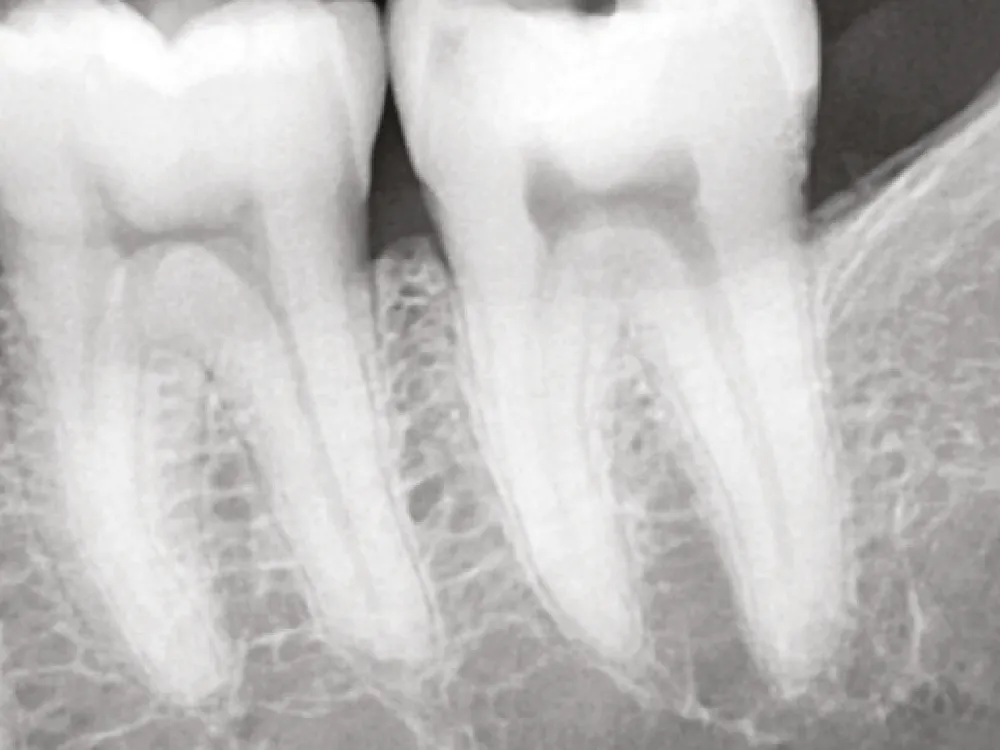

1

Avant le traitement

2

Application du One-Fil Putty Injectable

3

Après le traitement